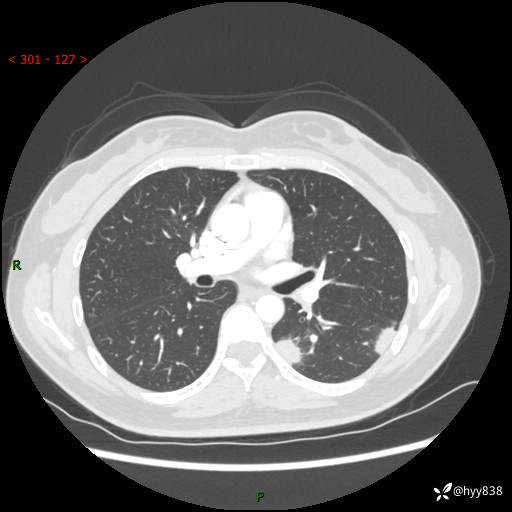

【患者信息】:36岁/女

【主诉】:左侧下胸部阵发性疼痛2周,乏力1周

【现病史及既往史】:患者自诉2周前饮酒后出现左侧下胸部阵发性疼痛,不随呼吸改变,无咳嗽咳痰、头晕头痛、咳血、呼吸困难等不适,于当地第一人民医院查胸部CT提示肺部感染,随后前往我院门诊给予抗感染(左氧氟沙星)治疗1周,自诉胸痛较前好转,感乏力、头晕,偶尔干咳,无咳痰,无发热、畏寒、胸闷、咯血、四肢酸痛、腹泻、腹痛等不适,门诊复查胸部CT提示:左肺下叶感染,病灶较前增加增大,遂以“肺部感染”收入我科。 起病以来,患者精神、饮食、睡眠可,大小便正常,体力体重无明显变化。

【检查】:胸部CT增强(外院平扫)